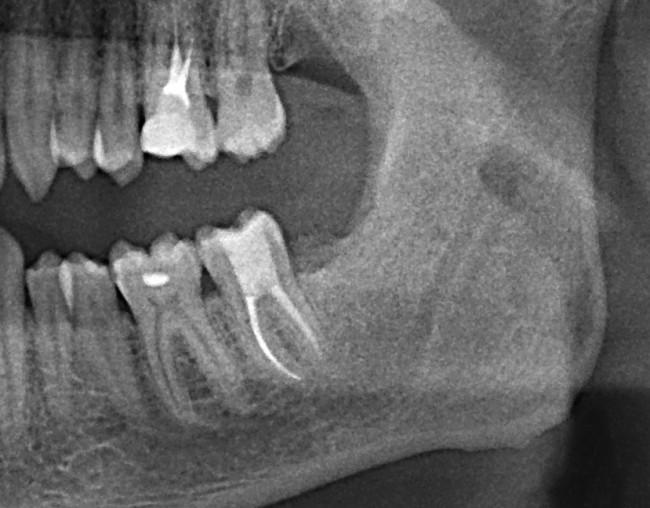

Вот снимок, примерно, через год после удаления.

Ни от зуба, ни от кисты не осталось и следа. Чего мы и хотели добиться.